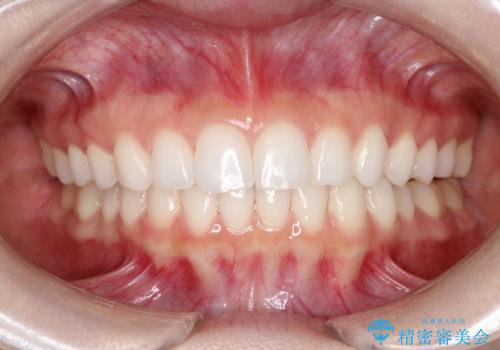

出っ歯の矯正治療 歯を抜かずにインビザラインで

- インビザラインで出っ歯を治したいとの希望がありました。

上顎の歯を全体的に後方に移動させて前歯を引っ込める計画としました。

インビザラインで目立たずに、痛みも少なく矯正治療を終えることができ満足していただけました。